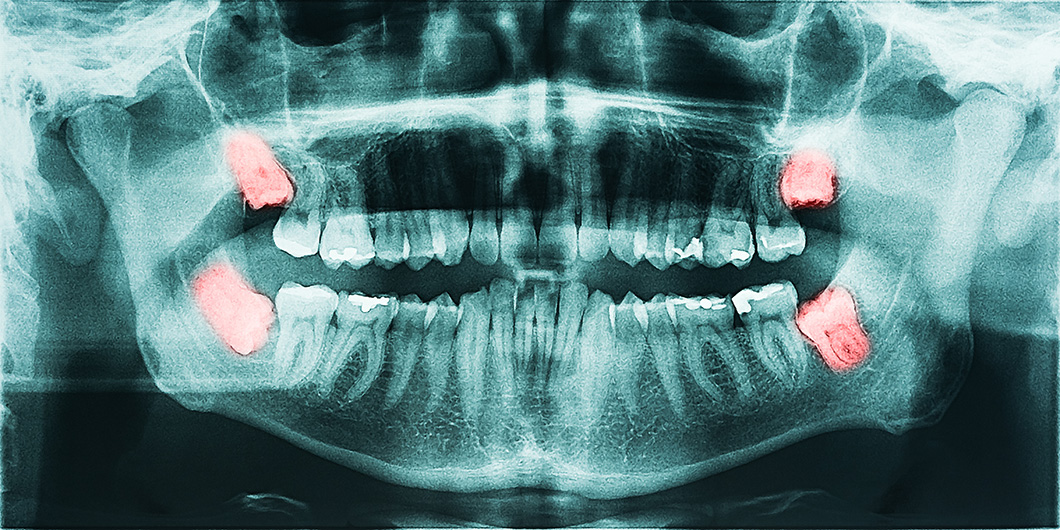

Sometimes it is necessary to extract a tooth. This can happen for a variety of reasons. Extractions are commonly performed in cases where a deciduous “baby” tooth is reluctant to fall out, a severely broken down and non-restorable tooth is present, or “wisdom tooth” is poorly positioned and unable to fully erupt into place.

Pano xray